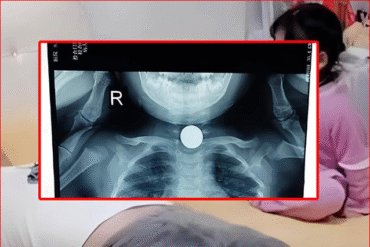

เศร้ามาก ผลชันสูตร “ตี๋” เหยื่อช่างเอก สาเหตุดับยิ่งสลดหนัก

เปิดผลชันสูตรเบื้องต้น สาเหตุการเสียชีวิตของตี๋ หนุ่ม 26 ปี เหยื่อช่างเอกร่วมมือกับเมีย 2 คน รุมดับคาร้านทำผม คืบหน้ากรณีเมื่อวันที่ 17 เมษายน 2569 ช่างเอก ช่างตัดผม อายุ 59 ปี ร่วมกับภรรยา 2 คน ก่อเหตุรุมทำร้าย ตี๋ หนุ่ม 26 ปี เสียชีวิตคาร้านตัดผมโดยอ้างว่าใช้สากลงมือเพื่อป้องกันตัวเนื่องจากผู้เสียชีวิตเข้ามาข่มขู่ขอยืมเงินและถือมีดเข้ามาด้วย ทว่าขัดแย้งกับคำให้การของพยานหนึ่งเดียวในร้านคือลูกค้าวัย 15…